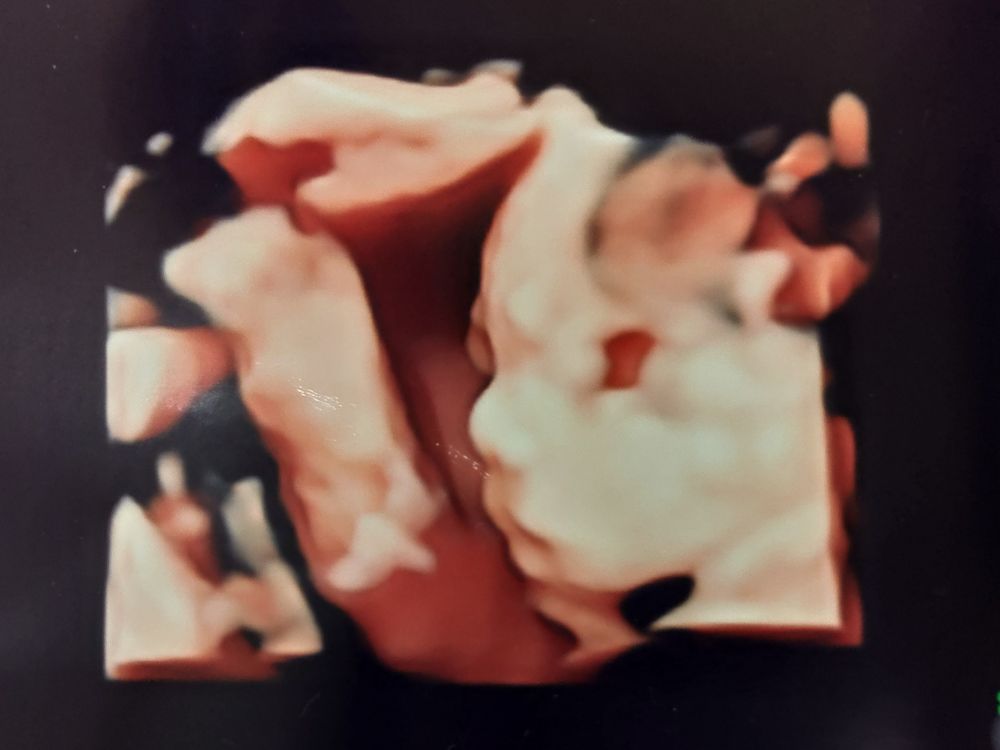

28wの妊婦健診。赤ちゃんは順調に成長!

今回も助産師さんのエコーのみ。順調で一安心

今回の28w健診も、前回に引き続き特に問題がなかったため

助産師さんによるエコーと採血(血糖値・貧血)の診察でした。

赤ちゃんの推定体重も774g(25w)→1199g(28w)と3週間で約400gほど大きくなっていました。

口をパクパクしている姿も見られ、前回より顔の肉付きも良くなってきたようでした。最近の胎動も力強く寝れないくらいなので、元気でなによりです。